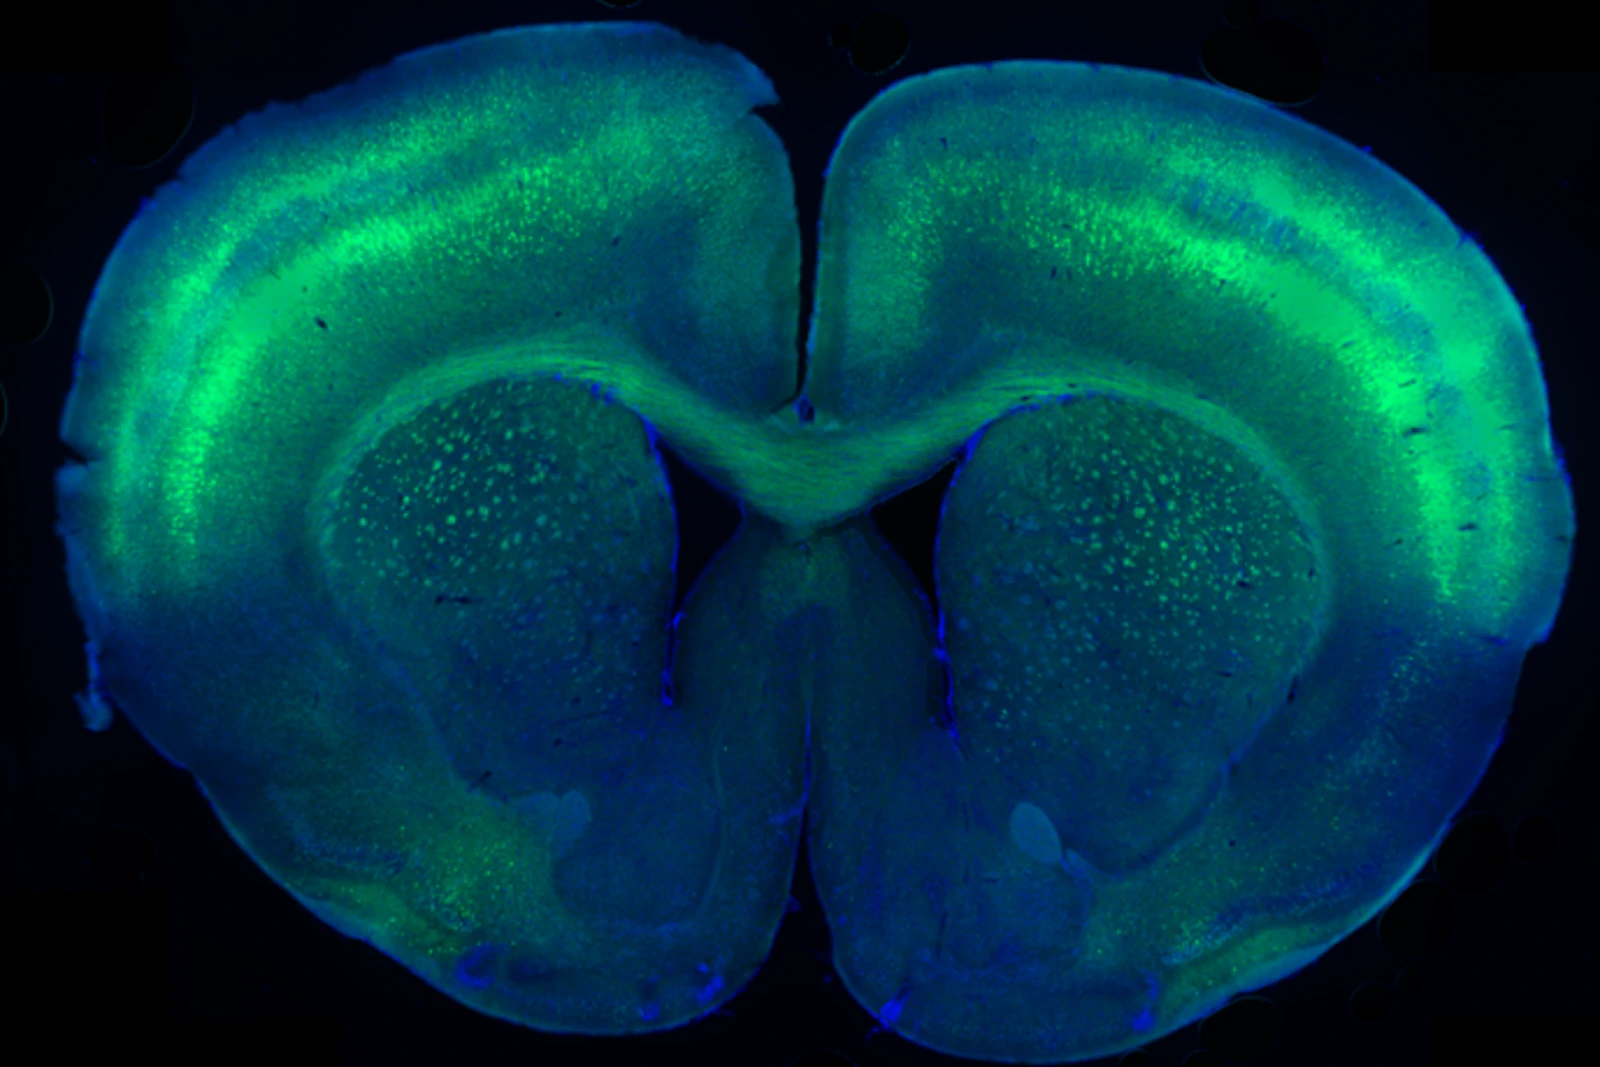

UCLA Health医疗中心美泰儿童医院儿科神经学专家Shaun Hussain博士

05 UCLA Health医疗中心美泰儿童医院儿科神经学专家Shaun Hussain博士